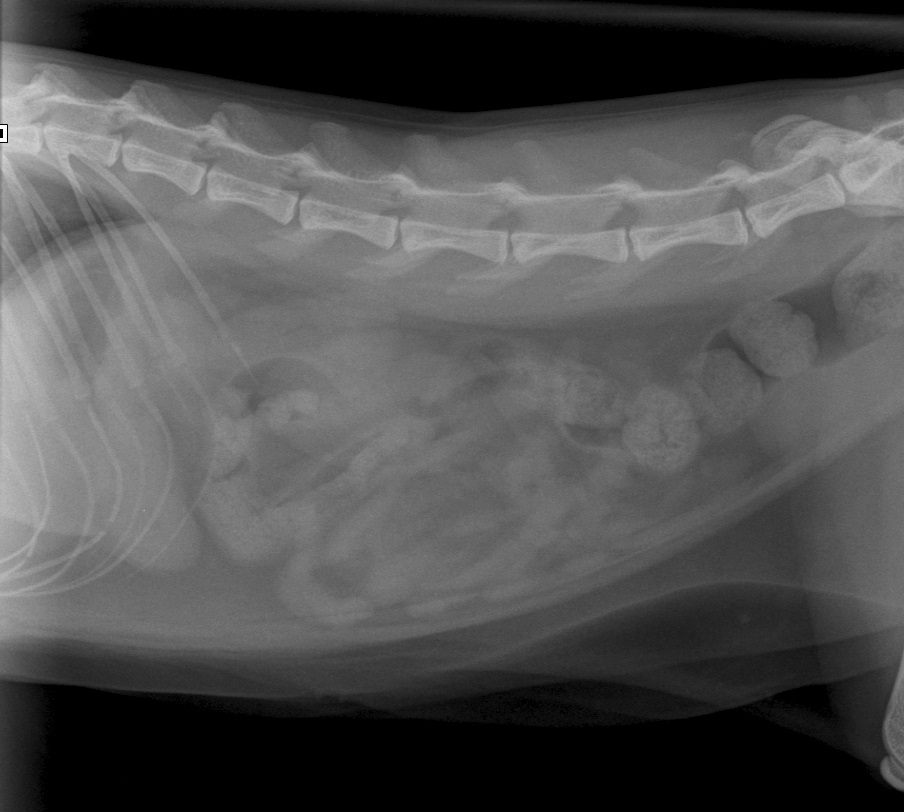

De buik van Noortje op de röntgenfoto

Op 11 augustus 2015 kwam de drie jaar oude poes Noortje op het spreekuur omdat ze zich niet lekker voelde. Ze had meerdere keren gebraakt en alleen een beetje water bleef binnen. Ze was verder iets rustiger dan normaal, maar zeker niet doodziek. We hebben haar goed onderzocht en afgezien van een iets gevoelige buik vertoonde Noortje geen afwijkingen. Voor de zekerheid hebben we een röntgenfoto van haar buik gemaakt en daar waren geen grove afwijkingen op te zien.